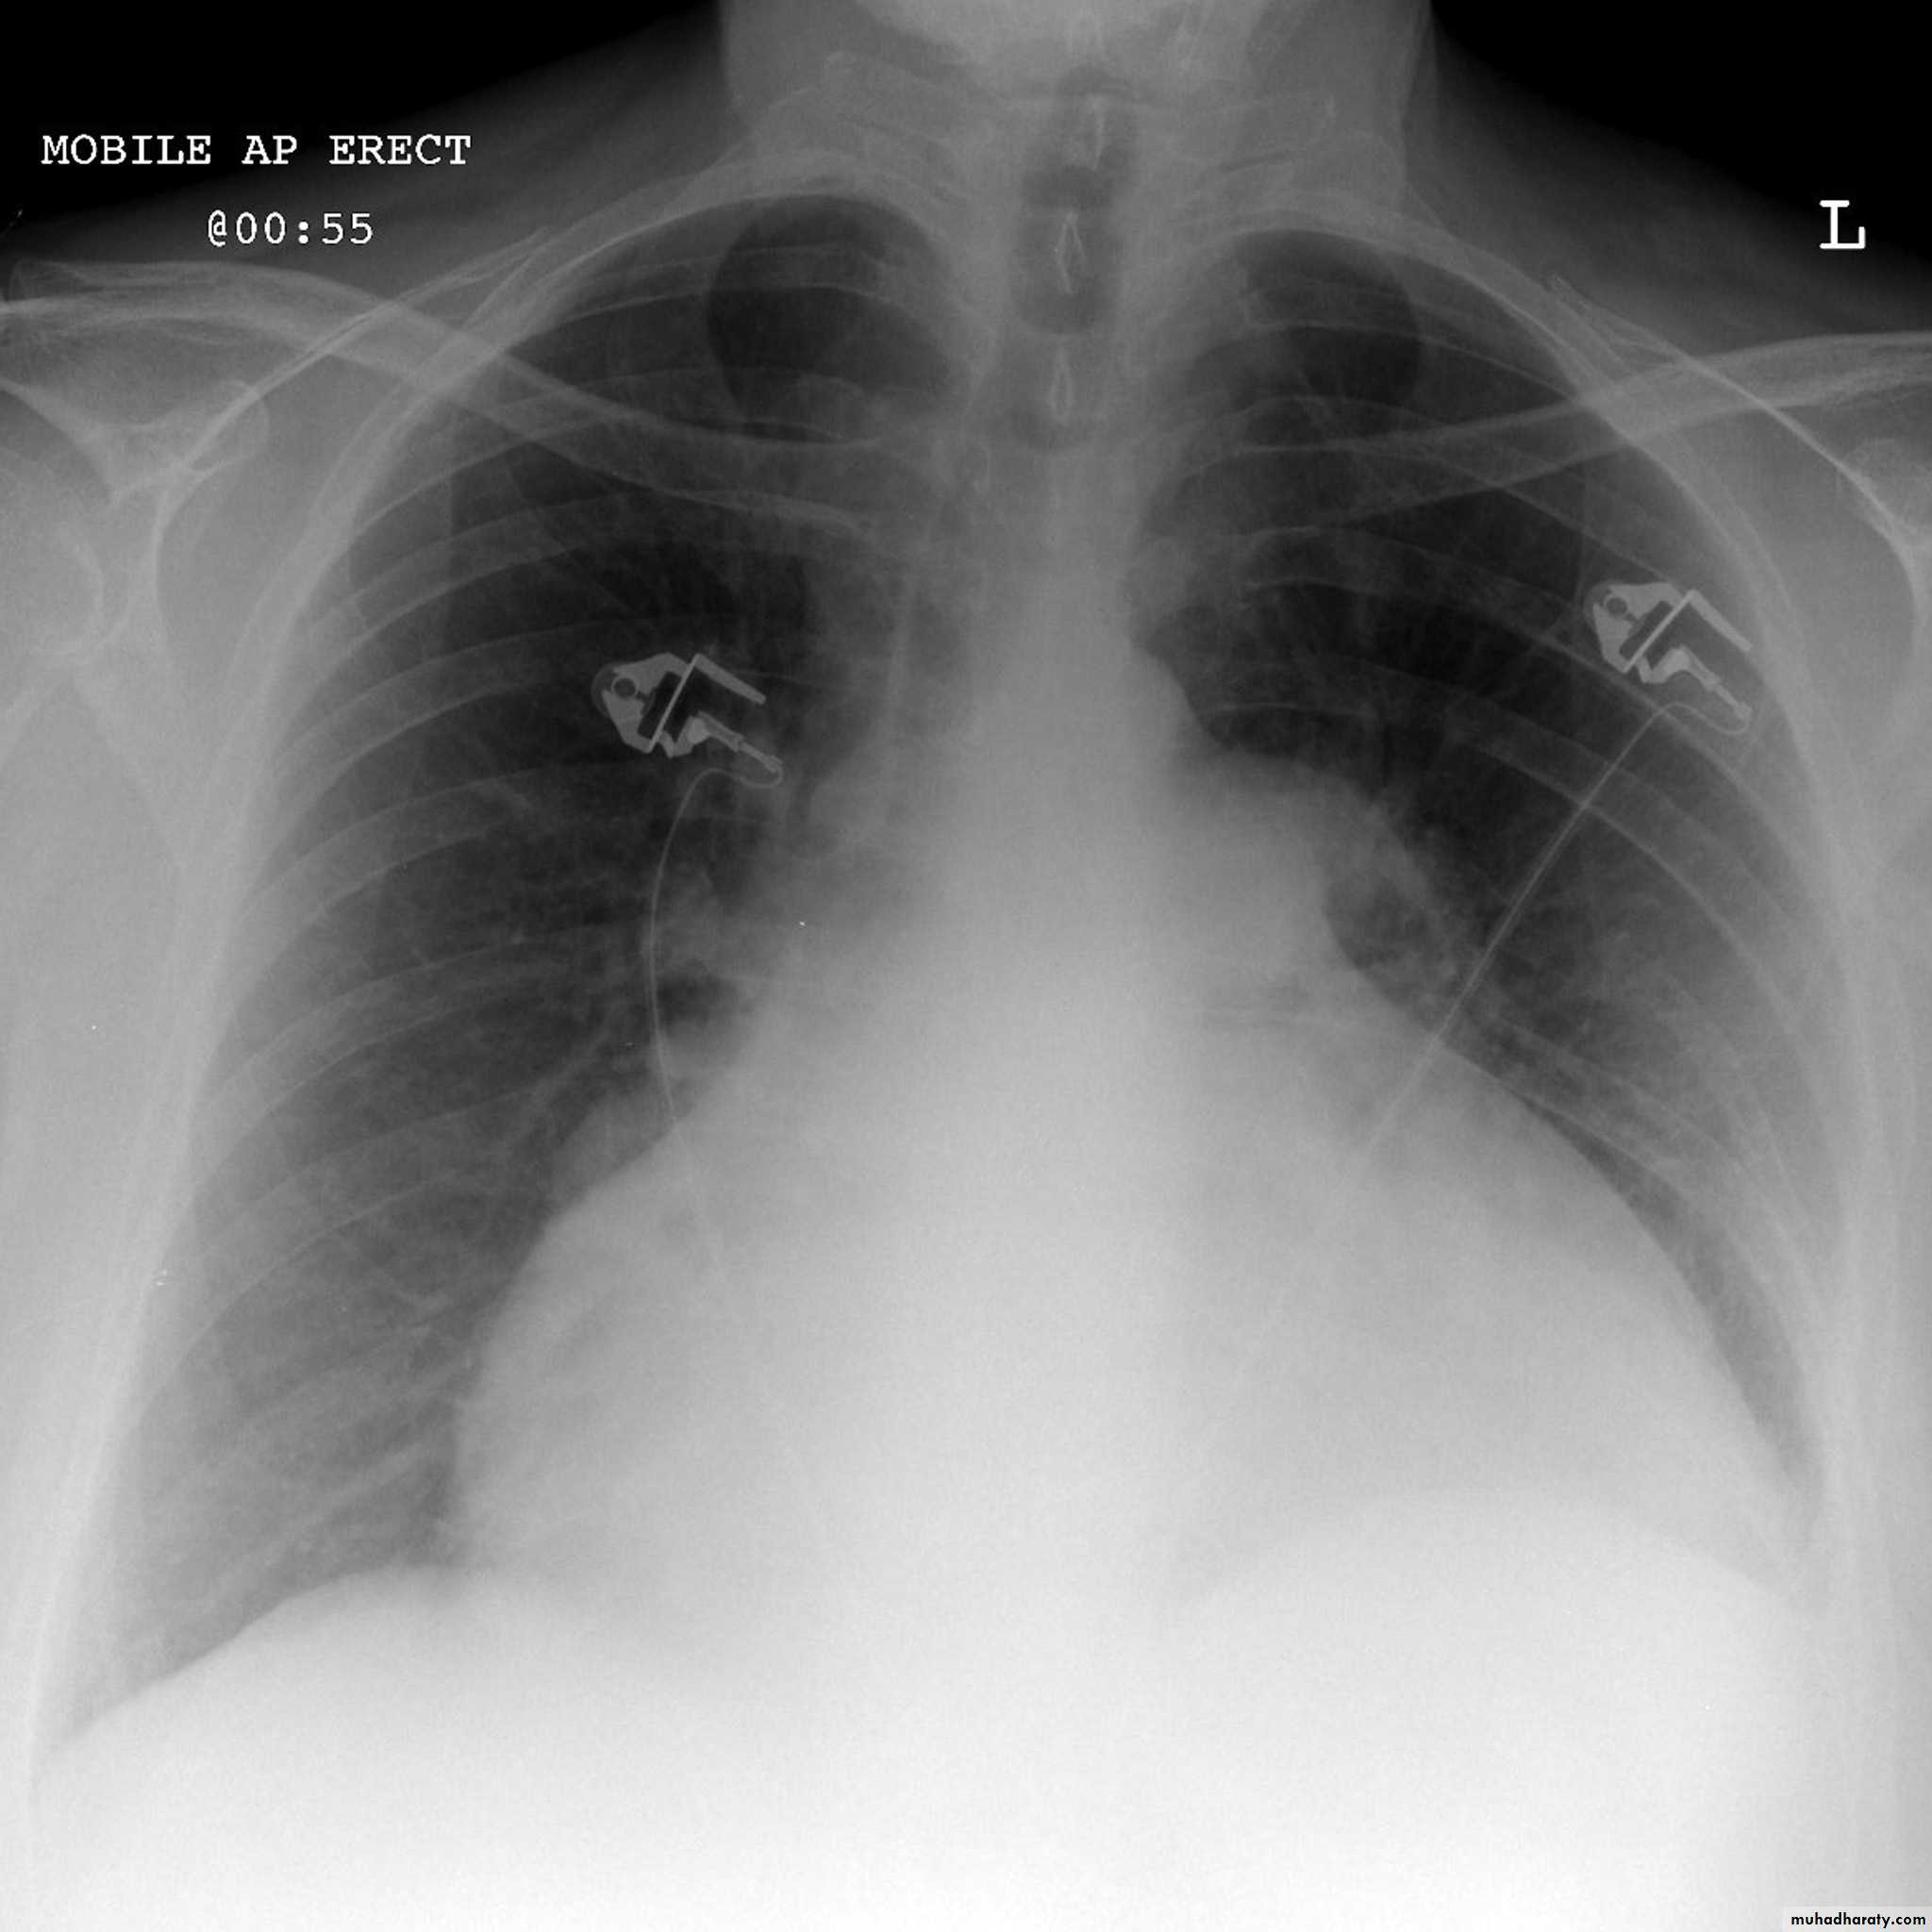

Cardiothoracic ratio (CTR) = Cardiac Width : Thoracic Width

A CTR of greater than 1:2 (50%) is considered abnormal. This however, assumes the projection is Posterior-Anterior (PA), and that cardiac size is not exaggerated by factors such as patient rotation or an incomplete breath in .

The cardiothoracic ratio aids in the detection of cardiomegaly, or more broadly, enlargement of the cardiac silhouette. .

Enlargement of the cardiac silhouette on chest x-ray can be due to a number of causes :

cardiomegaly (most common cause by far)pericardial effusion

anterior mediastinal massprominent epicardial fat pad

Congestive cardiac failure (CCF) is a form of cardiac failure which is primarily manifested by the heart inability to pump the volume of blood. It can affect the left (common) or right cardiac chambers or both.

Radiographic features

Chest radiograph

With left sided congestive cardiac failure, the features are that of pulmonary edema which includes:

central pulmonary venous congestion ( prominent hilum )

cephalization of pulmonary veins ( upper lobe pulmonary venous diversion )

pulmonary interstitial edema

pulmonary alveolar edema

Cardiomegaly

Pleural effusion

Pericardial effusions occur when fluid collects in the pericardial space (a normal pericardial sac contains approximately 30-50 mL of fluid).

Plain radiographa very small pericardial effusion can be occult on plain film

there can be globular enlargement of the cardiac shadow giving a water bottle configuration known as Globe shape heart or pumpkin shape heart .

Pericardial effusion